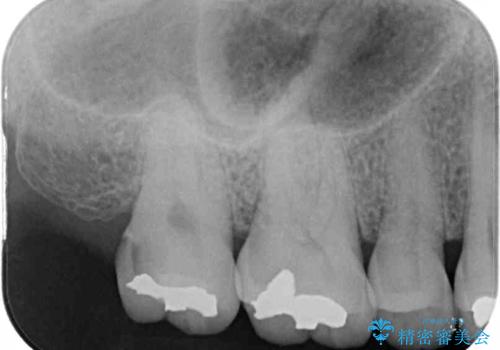

- 奥歯に装着されてい銀歯の中が虫歯になってしまったとのことで来院された患者様です。

虫歯をしっかりと取り除き、ゴールドインレー(PGAインレー)にて修復することとしました。